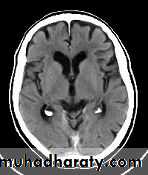

Normal Ventricles

35

Hydrocephalus